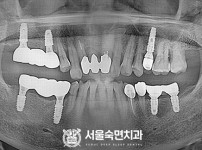

임플란트-전후사진2

치과를-선택할-때-꼭-확인하세요-서울숙면치과-임플란트-전후사진